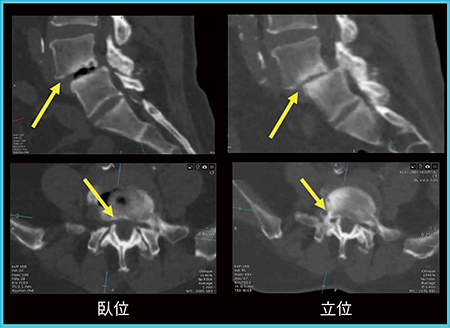

図3は脊椎すべり症で,臥位では無症状であるが,立位では痛みを生じる症例である。整形外科医からは,立位CT画像を術前に確認することで,自信を持って治療部位の同定が可能であると高い評価が得られた。

図3 脊椎すべり症の術前評価